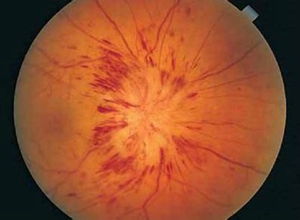

白塞氏眼睛病变图片,眼睛黄斑病变的图片

眼睛黄斑病变的图片

黄斑病变图片

黄斑病变